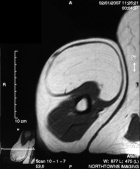

G.O. - 75 year old male with a right upper arm mass for 25 years; the mass never bothered him until a few months ago when he began having intermittent discomfort, he does not think the mass has grown recently